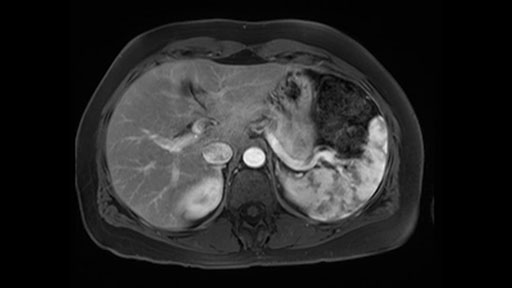

In reviewing this patient’s CT scan, first of all, the lesion is again cystic with a very thin wall. I anticipate that it will be delicate and potentially friable. And therefore the risk of rupture exists and we need to be very careful in how we handle the pancreas and the tumor throughout the procedure.

The lesion itself is quite adjacent to and abuts the splenic vein and therefore we need to anticipate that these two structures will be intimately related and possibly impossible to separate between the two.

The lesion also is quite posterior. While the plane between the cyst and the left adrenal gland is often preserved, we do have to pay attention here so that we remain in the right plane and maintain our margin here. Occasionally in these cases, en bloc adrenalectomy needs to be performed.

In terms of maintenance of the regular planes, other factors that we need to consider is whether you need to enter in posteriorly to Gerota’s fascia to obtain an adequate margin and anteriorly to ensure the tumor can be mobilized safely off of the posterior wall of the stomach.

In light of these findings, on the cross sectional imaging which include MRI, our plan would be to perform a laparoscopic distal pancreatectomy. I think based on oncologic grounds, a spleen preserving procedure is probably reasonable. From looking at the scan, its likely technically possible although a vessel preserving procedure is likely not appropriate for this patient. Technical intraoperative factors will certainly influence that decision.